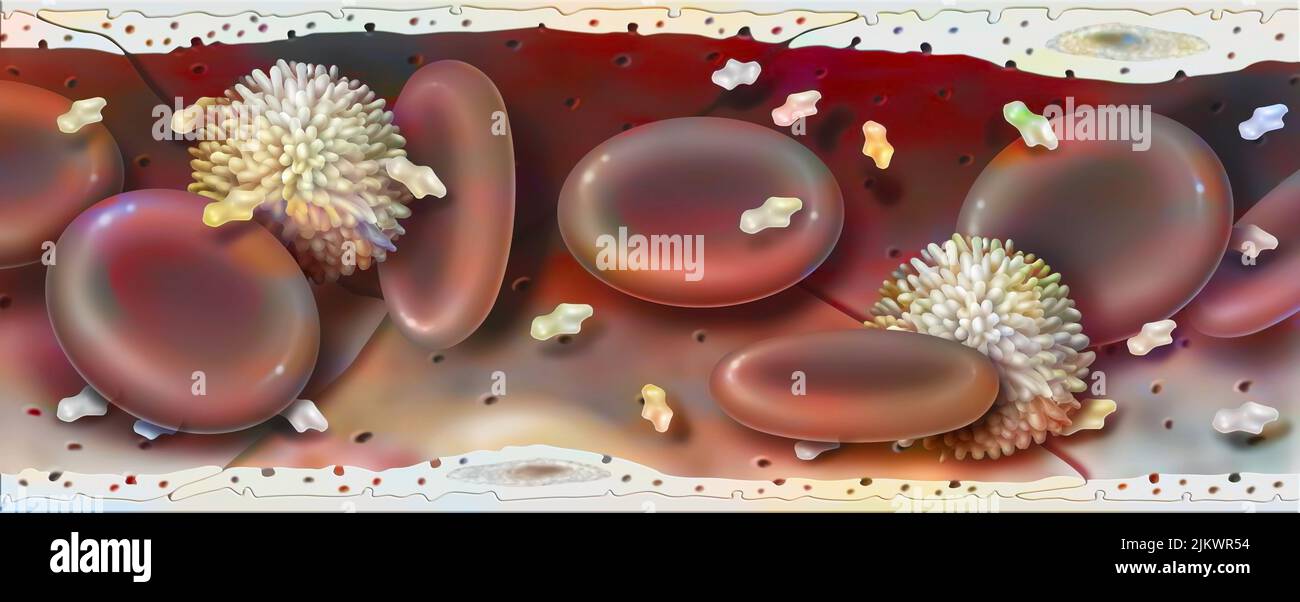

RF2JKWR54–Vaisseau sanguin contenant des globules rouges, des globules blancs, des plaquettes et du plasma.